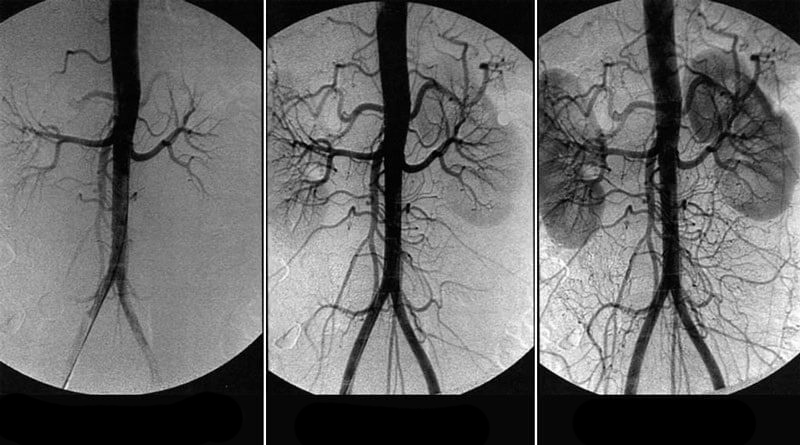

• Arterias renales

Las lesiones ateroscleróticas de los vasos que irrigan los riñones desarrollan una arteriosclerosis secundaria. Las manifestaciones características son el edema que se forma debido a la retención de sodio en el organismo, siendo la situación más difícil el desarrollo del edema pulmonar. Una de las consecuencias es el infarto renal. Cuando un riñón está afectado, los síntomas no son pronunciados.

Hipertensión renal

Renal hypertension

Riñón con suministro de sangre normal

Riñón con suministro de sangre alterado

Una obstrucción de colesterol en una arteria renal provoca una insuficiencia renal aguda.

Las principales manifestaciones de la aterosclerosis de las arterias renales:

• hipertensión;

• hinchazón;

• dolores localizados en la zona de la espalda;

• debilidad, pérdida de fuerzas.